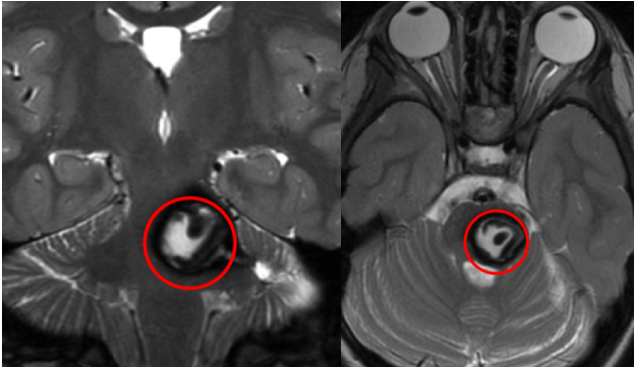

头颅核磁共振检查结果显示:中脑脑干部位存在占位性病变,呈现混杂信号,考虑为海绵状血管瘤的可能性较大。影像学特征表明这符合反复少量出血后的改变,这意味着在此之前,晶晶可能已经发生过几次轻微的脑干出血,但没有造成明显的神经功能损伤。

最终,手术在不久后进行,主刀医生是巴特朗菲教授。手术采取颞下入路进入中脑脑干侧面,全程使用神经电生理监测,实时评估运动功能、感觉功能以及颅神经功能。巴教授以液化的血肿为引导,清晰辨认病变与正常脑干组织的界面,完成完整剥离,手术顺利完成。

术后立即进行影像学复查确认:病变实现镜下全切,手术区域没有新发出血,没有明显水肿,瘤腔内可见止血材料正常显影。